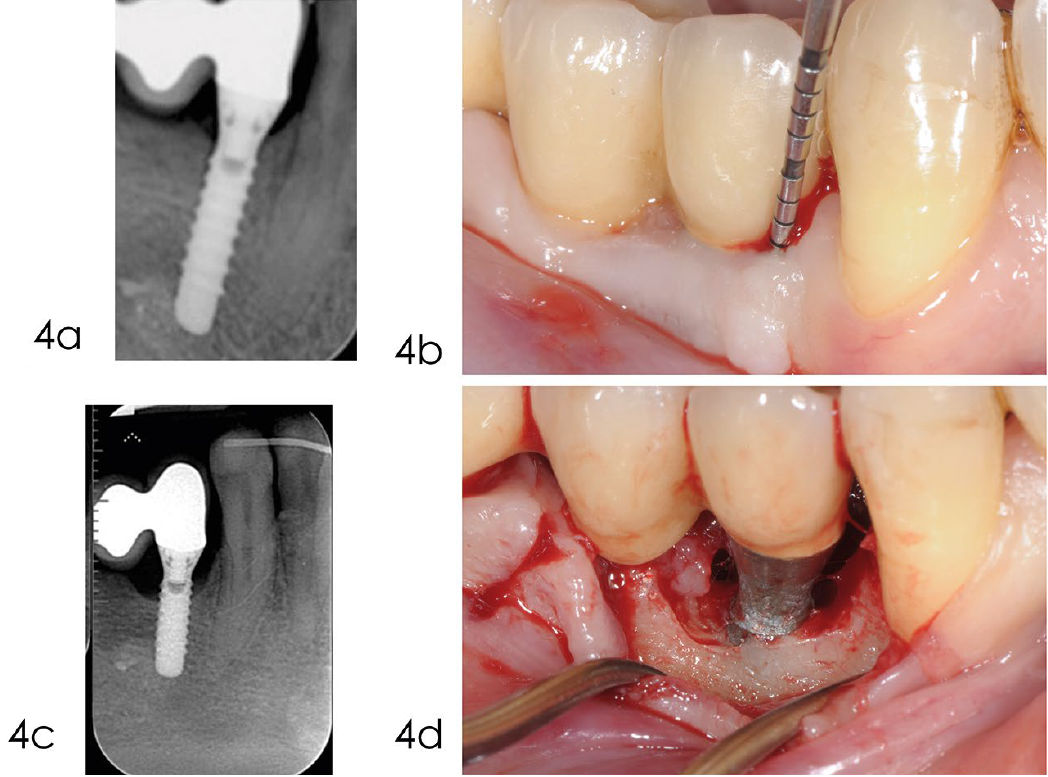

Фото 4. Обработка с доступом через лоскут

a) Рентгенограмма, выполненная через год после установки протеза, показывает оптимальный уровень кости вокруг имплантата. b) Кровоточивость при лёгком зондировании и глубина кармана 6 мм через пять лет после установки имплантата. c) Рентгенограмма, выполненная в декабре 2014 года, показывает краевую убыль кости в области имплантата 4.4. d) При отслаивании полнослойного лоскута выявлена убыль кости на уровне второго витка. Из-за тонкого костного гребня без внутриостного компонента было принято решение отказаться от реконструктивного подхода в пользу открытой инструментальной обработки

Фото 5. a) После удаления грануляционной ткани поверхность имплантата была обработана 24% ЭДТА в течение двух минут. b) После промывания физиологическим раствором на поверхность нанесён гель хлоргексидина 1% на две минуты. c) Шов нитью Vicryl 4/0 обеспечивает оптимальное открытое (непогружённое) заживление. d) Заживление проходит без осложнений

Фото 6. a) Рентгенограмма, выполненная в сентябре 2020 года, через десять лет после установки имплантата, показывает стабильный костный дефект. b) Клиническое изображение, сделанное в сентябре 2020 года, демонстрирует отсутствие воспаления в мягких тканях вокруг имплантата. c) Рентгенограмма, выполненная в январе 2024 года, подтверждает отсутствие дальнейшей потери кости дистально и небольшое улучшение с мезиальной стороны. d) Клиническое изображение, сделанное в январе 2024 года, показывает минимальную рецессию мягких тканей через 14 лет после установки имплантата. Зондирование выявляет стабильную, хотя и не идеальную, глубину пародонтального кармана